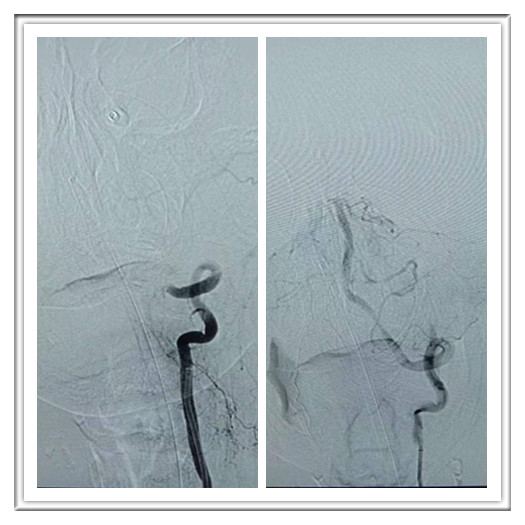

2019年3月15日,对于军工医院神经内科来说,是一个值得纪念的日子。晚上19点,神经内科在急诊介入中心成功救治一位急性脑梗死患者。手术的成功完成,表明军工医院脑血管病的治疗再上新的台阶,急性脑梗死从静脉溶栓到血管内支架植入、取栓等均能完成。

青龙县69岁男性患者张某,晨起上厕所时自感无力、头晕,随即倒地,家属立刻将他送到青龙县医院,6小时后转入秦皇岛军工医院。神经内科副主任李光雷给予查体,患者呈浅昏迷状态,右侧肢体肌力0级,左侧肢体肌力差,双侧病理征阳性,头CT未见出血。诊断为急性脑梗死。患者到院时间已超出静脉溶栓最佳时间窗口,但仍在血管内治疗时间内。李主任即刻向家属交代病情及下一步的治疗方案,家属表示理解并同意治疗。在神经外科、麻醉科和放射科医护人员的全力配合下,经过3个多小时的精密手术,将堵塞的椎动脉V4段和基底动脉完全再通。术后患者清醒,能完成指令,右侧肢体由0级变为2级。